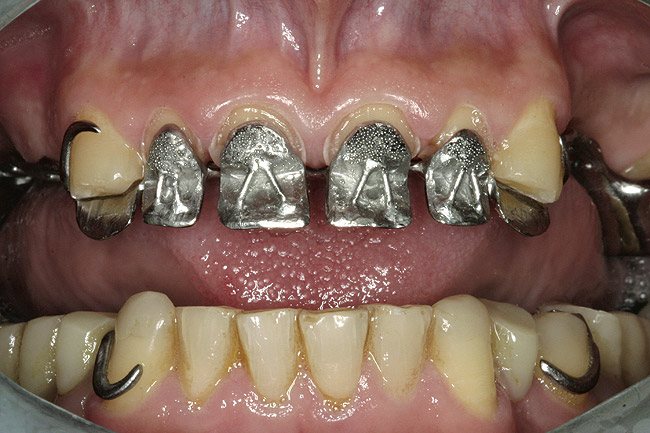

Figure 12  Maxillary prosthesis framework.

Figure 12

The casts were surveyed to determine the most suitable path of insertion for the definitive prosthesis. The posterior occlusal surfaces were waxed, and wax patterns were used for clasps and denture base connectors. Retentions were placed on the surfaces of the anterior portion of the framework to support acrylic veneers. The wax patterns were casted in a chrome-cobalt alloy (Figure 12).

The design of the final maxillary overlay Cr-Co framework included metal occlusal surfaces on the anterior teeth and left second maxillary molar, a telescopic crown on the right maxillary third molar, circumferential clasps on the canines and left second molar, and a palatal strap as a major connector. Metal occlusal surfaces on the incisive teeth were provided with retention beads for an acrylic resin veneer material in the facial aspect of the incisors, and the tip of the canines were restored with composite resin to avoid further tooth surface preparation and to maintain maximum proprioception.

The framework was evaluated intraorally for fit, occlusion, retention, and stability (Figure 13, Figure 14 and Figure 15). With the framework in position, a new maxillo–mandibular relationship record was made with a silicone-based interocclusal record material, and the definitive casts were remounted on the articulator. The framework was returned to the laboratory, and acrylic resin veneers were applied in the esthetic zone and posterior artificial acrylic resin teeth were placed on the framework. The artificial teeth were arranged and tried in to verify esthetics and jaw relation records and to obtain the patient's approval before final processing. The junction between the maxillary natural teeth and the overlay prosthesis was not noticeable during normal speech and function.